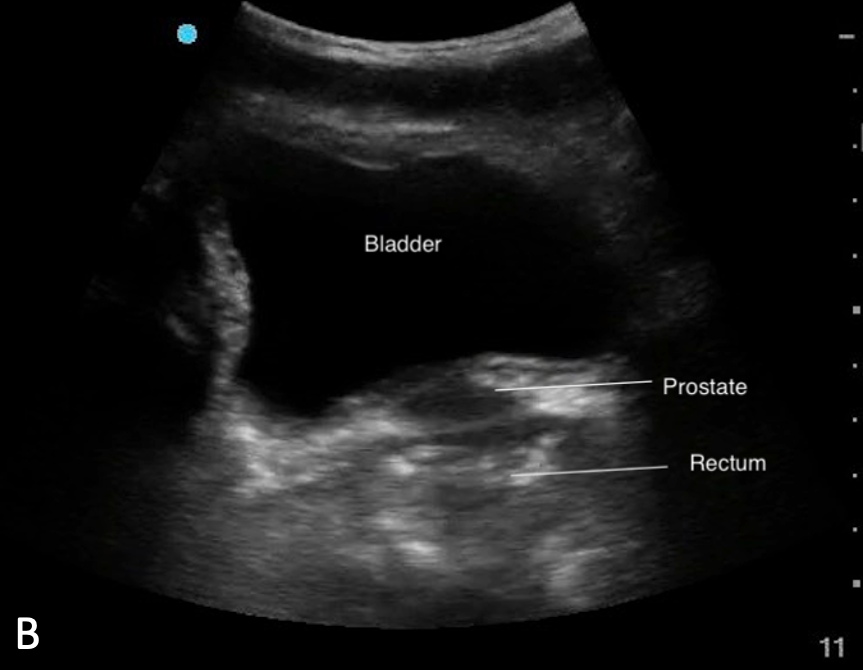

– Sits cranial and anterior to the prostate in males (Figure 7b,9b)

Figure 7ab: Sagittal bladder sonoanatomy in female (a) and male (b) children.

Figure 9ab: Transverse bladder scan sonoanatomy in female (a) and male (b) chidlren.